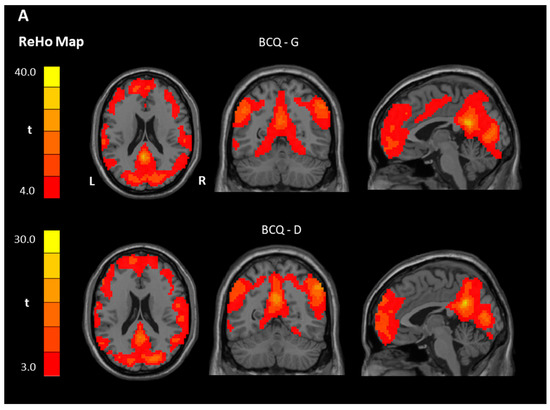

3.3. ReHo and ALFF Analyses

| Contrast | Region | BA | Size | t Score | Peak Coordinate | ||

|---|---|---|---|---|---|---|---|

| x | y | z | |||||

| ReHo | |||||||

| Within-group ** | |||||||

| BCQ-Gentleness | |||||||

| Gentleness > 0 | PCC, Left | 23 | 16,838 | 33.85 | −3 | −48 | 24 |

| Gentleness < 0 | NS | ||||||

| BCQ-Deficiency | |||||||

| Deficiency > 0 | PCC, Left | 23 | 8516 | 30.36 | −3 | −54 | 30 |

| OFC, Right | 11 | 4593 | 21.54 | 42 | 52 | −12 | |

| Deficiency < 0 | NS | ||||||

| Between-group * | |||||||

| Gentleness > Deficiency | Postcentral gyrus | 2 | 69 | 5.37 | 51 | −24 | 45 |

| Gentleness < Deficiency | NS | ||||||